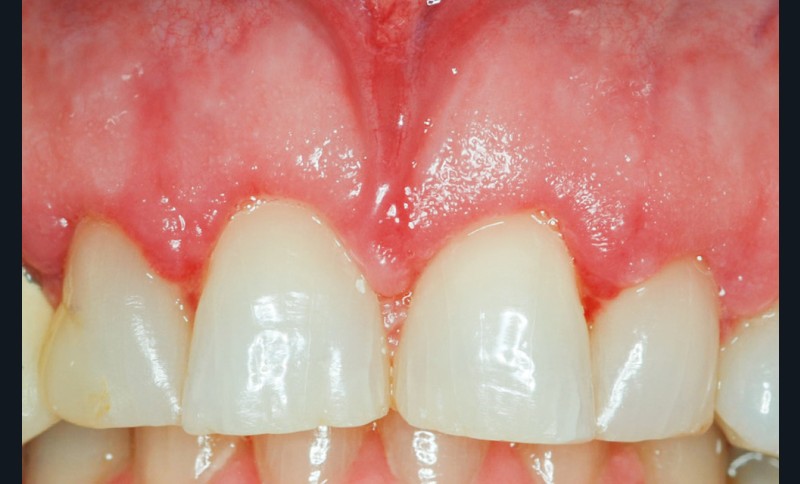

Même en l’absence de restauration, l’espace biologique n’est parfois naturellement pas correctement établi sur la dent. Ce phénomène est couramment décrit comme une éruption passive retardée. Elle peut être une indication d’élongation coronaire esthétique afin de rétablir la couronne clinique dans son intégralité (fig. 2a-c).

2 – L’élongation coronaire se fera aux dépens du parodonte superficiel et du parodonte profond. Une gingivectomie n’est possible que si le parodonte comporte plus de 3 mm de gencive kératinisée. En effet, il est recommandé…